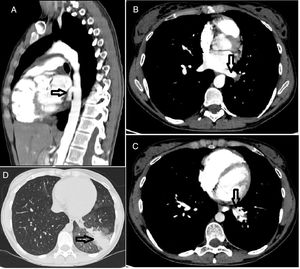

Chest computed tomography and angiography with sagittal (A) and axial (B) reconstructions showing: A (arrow) – an abnormal artery from the thoracic aorta to supply the left lower lobe of the lung; B (arrow) – the left inferior pulmonary vein receiving the drainage from the lobe defining an intralobar sequestration; C (arrow) – both the aberrant artery branch (#) and the inferior pulmonary vein (*) parallel to each other; D (arrow) – a heterogeneous density of the pulmonary parenchyma surrounded by ground glass opacity corresponding to the affected left lower lobe of the lung.

She was admitted for aetiological investigation. Pulmonary sequestration was suspected and an early chest computed tomography and angiography was performed without need for further investigation since it revealed an intralobar pulmonary sequestration, with arterial supply from a thoracic aortic branch (Fig. 1) and venous drainage into pulmonary veins. Her respiratory function tests were normal.